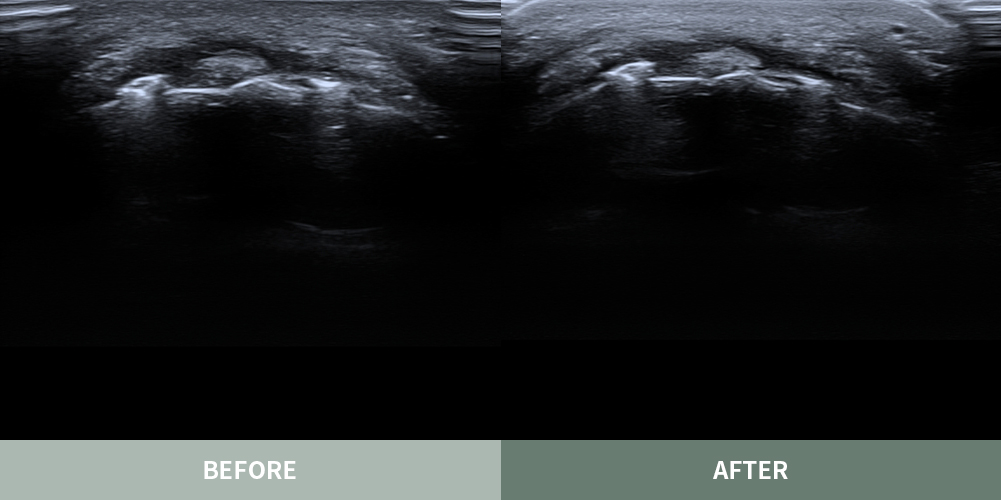

마이너스핏 프로그램은 얼굴이나 몸의 유착 조직이나 섬유화된 결절 부위를

초음파로 정밀하게 진단 후 부작용이 발생하기 전의 자연스럽고

아름다운 본래의 피부로 복원하는 흉살 치료 프로그램입니다.

대표원장 촉진 및 초음파 진단

흉살 조직에 대한 경험과 이해가 풍부한 고정아 대표원장이

부작용의 상태를 직접 파악하고 정확하게 진단합니다.